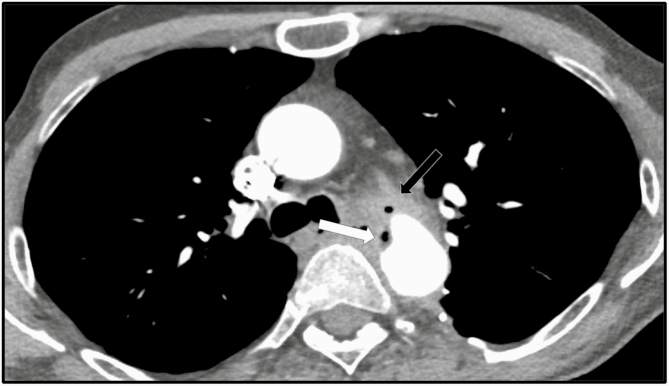

The patient is a 49-year-old man with no significant medical history, who initially presented to the hospital with a traumatic thoracic aortic tear due to a motor vehicle accident in 2000 requiring emergent thoracic aortic graft repair and splenectomy. In June 2017, he presented to the hospital with fever and chills. Workup revealed thoracic aortic graft infection (Figure 1) and an aorto-bronchial fistula involving the aortic graft; he then underwent resection of the left upper lobe of the lung, explantation of the infected aortic graft, and placement of a new thoracic aortic Dacron graft. Cultures from the explanted graft grew C. albicans, C. glabrata (Isolate 1, Table 1), and Lactobacillus paracasei. The postoperative course was complicated by chylothorax due to disruption of the thoracic duct, which required embolization with multiple platinum-fibered coils. Antimicrobial therapy with intravenous (IV) piperacillin-tazobactam, IV vancomycin, and IV micafungin was completed after 6 weeks, and suppressive therapy with oral fluconazole 800 mg daily was begun, given the concern that the new graft was in a contaminated field.

Figure 1.

Axial CT angiogram sections below the level of the aortic arch, performed on June 11, 2017. Soft tissue thickening and stranding surrounding the descending thoracic aortic stent graft concerning for graft infection (black arrow). There is no mediastinal fluid collection. There is right lower lobe consolidation and/or collapse (white arrow) and small bilateral pleural effusions. Abbreviation: CT, computed tomography.